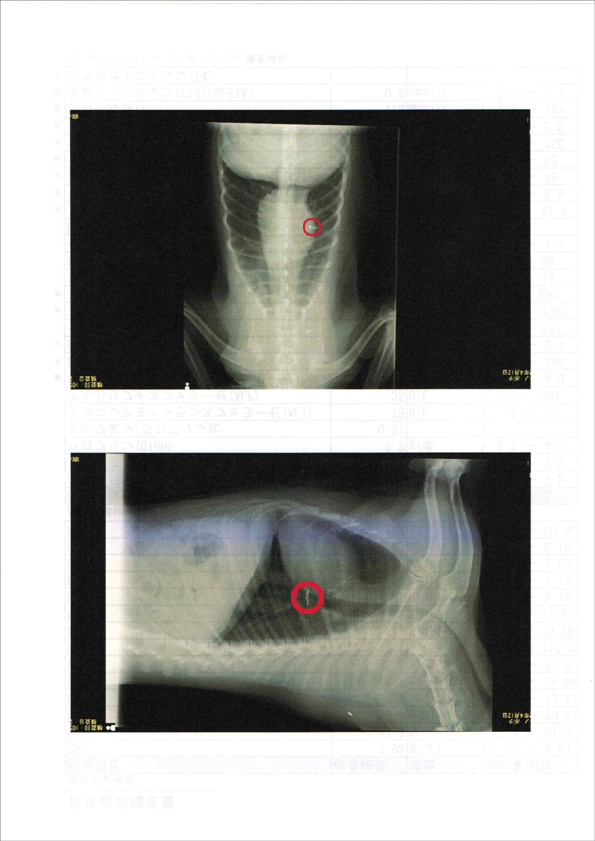

こちらが今回の健診の結果を載ったファイル。血液検査やレントゲン、エコーの画像などが掲載されています

胸部レントゲンの画像。赤丸のところが、以前手術した肺に埋め込まれた金属製のピンです